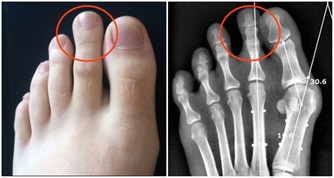

有「帝王病」之稱的痛風,是現代人常見的文明病之一,

引發原因大多為患者飲食過於豐富,經常大魚大肉,導致人體內尿酸生成過多,形成「高尿酸血症」。

中醫師黃慧娟指出,造成痛風的主要原因為民眾經常食用高普林(Purine)食物,

像是海鮮、動物內臟、豆類等,促使體內尿酸過高,造成新陳代謝異常,

進而形成尿酸鹽結晶,沉積在關節內,造成關節疼痛及腫脹。